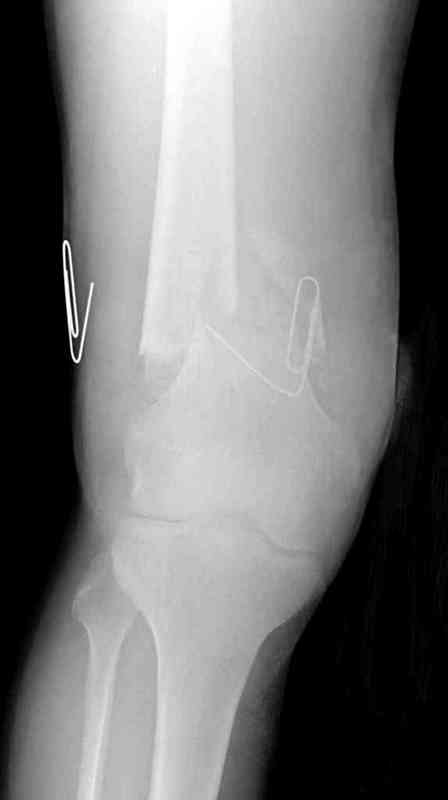

Больная К. с тугим ложным суставом н/3 бедра. Травма в 2005 г.-закрытый перелом, остеосинтез в аппарате Илизарова. В 2006 г. оперирована по поводу несросшегося перелома.

В ноябре 2006 г. демонтаж аппарата, после чего в течении месяца развилась вальгусная деформация. Имеется патологическая подвижность. Объем движений в коленном суставе 180-140. На обсуждение выносятся варианты лечения погружными конструкциями.

The patient with non-union of the distal femur. Trauma in 2005 - closed fracture of the femur, external fixation with Ilizarov apparatus. Non-union. In 2006 open reduction and external fixation with Ilizarov apparatus. In November 2006 the apparatus was removed, after that valgus deformation developed. There is pathological mobility. The knee motion 180-140. We'd like to discuss options of internal fixation.